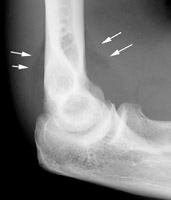

A. Normal lateral radiograph of the elbow. B. Plain film radiograph of the lateral elbow which reveals the classic elbow fat pad sign. This is an invaluable soft tissue finding in cases of intra-articular injury of the elbow. Fat is normally present within the joint capsule of the elbow, but outside the synovium. Typically "hidden" in the concavity of the olecranon and coronoid fossae, the fat is usually not visible on the lateral radiograph. However, injuries that produce intra-articular hemorrhage cause distension of the synovium and forces the fat out of the fossa, producing triangular radiolucent shadows anterior and posterior to the distal end of the humerus. When present in a patient with a history of acute trauma to the elbow, the fat pad sign indicates the presence of an intra-articular hemorrhage, which in turn is often associated with an intra-articular skeletal injury (usually the radial head in an adult).

Normal lateral rlbow - Click on the image for a larger versionALateral elbow - Click on the image for a larger versionB